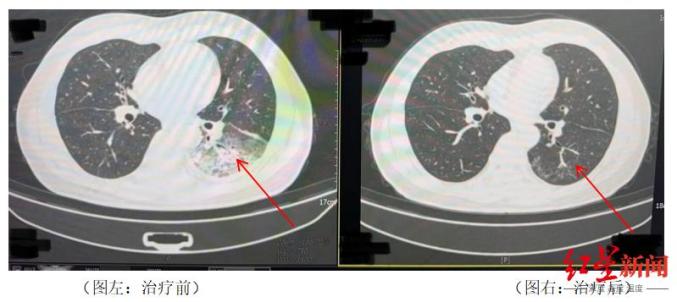

治疗前和治疗后李先生肺部的对比。

据悉,李先生开了3天空调后,出现了肌肉疼痛、头痛、发热、咳嗽等症状。起初,他以为是吹空调吹感冒,所以自己吃了感冒药,但是病情并没有好转,反而越来越严重。家人见此,立即将他送往成都市第五人民医院传染病科。胸部CT显示,李先生的左肺已经出现了大面积的白色图像,几乎占肺的一半。经肺泡灌洗NGS检测,最终确认“罪魁祸首”为嗜肺军团菌。